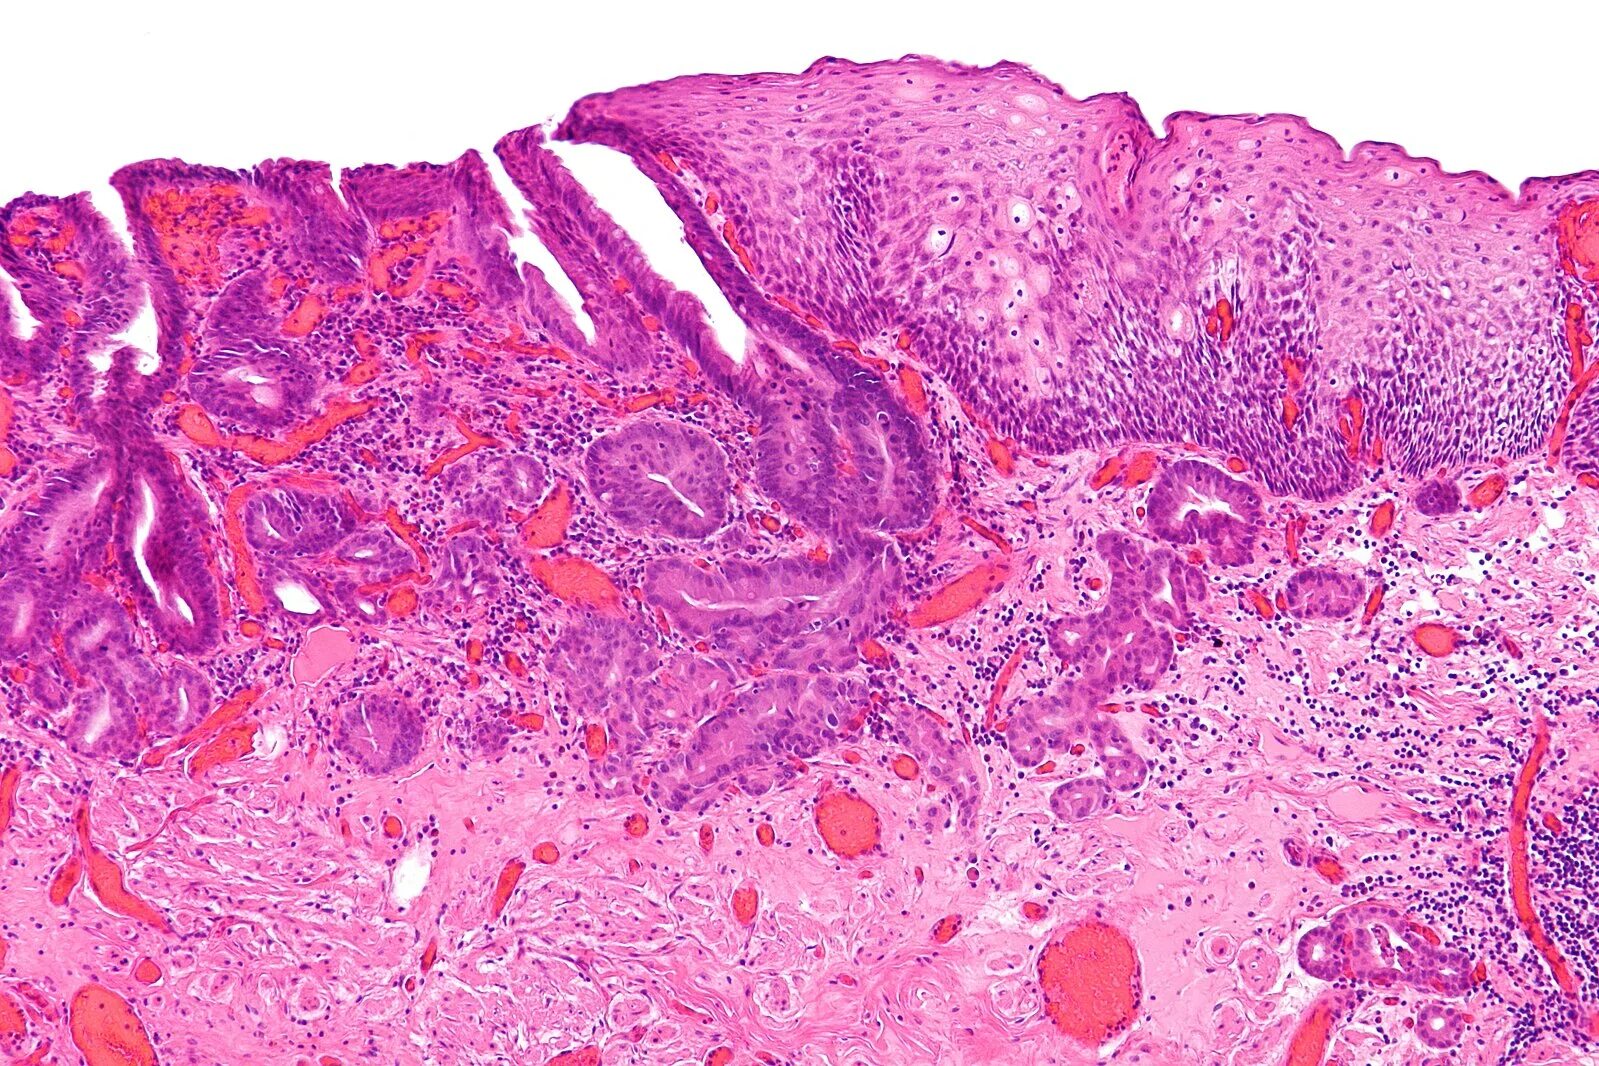

Гистологически аденокарцинома